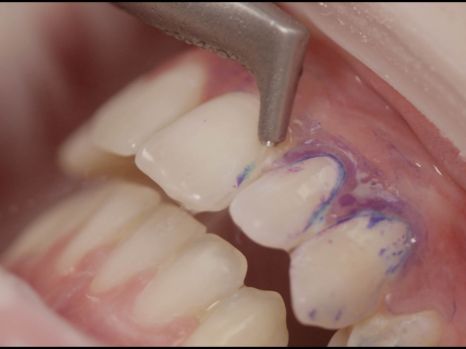

Unter dem Begriff „guided biofilm therapy - GBT“ haben wissenschaftliche Erkenntnisse und verfeinerte Techniken zu einer Weiterentwicklung in der professionellen Prophylaxe geführt.

DER MINIMAL INVASIVE WEG der Prophylaxe ist heute insbesondere beim noch weichen Biofilm Mittel der Wahl:

Neu entwickelte Pulver mit speziell abgestimmten Düsen entfernen Anhaftungen und Verfärbungen heute deutlich schonender!

So werden natürliche Zahnoberflächen aber auch Füllungen und Keramiken MAXIMAL geschont!